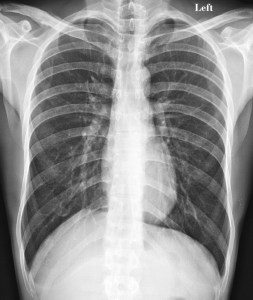

When Katherine first started to feel sick, she thought she had the flu or some other type of respiratory infection. She had a cough, trouble breathing, and chest pains. This is part of what makes mesothelioma so insidious. This is a cancer that attacks the lining of tissue around the lungs. It is most often caused by exposure to asbestos, but it does not develop into symptoms until decades after the exposure occurs.

In the meantime, people like Katherine have no idea that they are getting sick. When they do start to experience symptoms, they are often diagnosed as having an infection, pneumonia, or even lung cancer. Luckily for Katherine, although she was not diagnosed correctly right away, she still received her diagnosis when the cancer was in an early stage. Others are not so lucky and do not get an accurate diagnosis until much later.